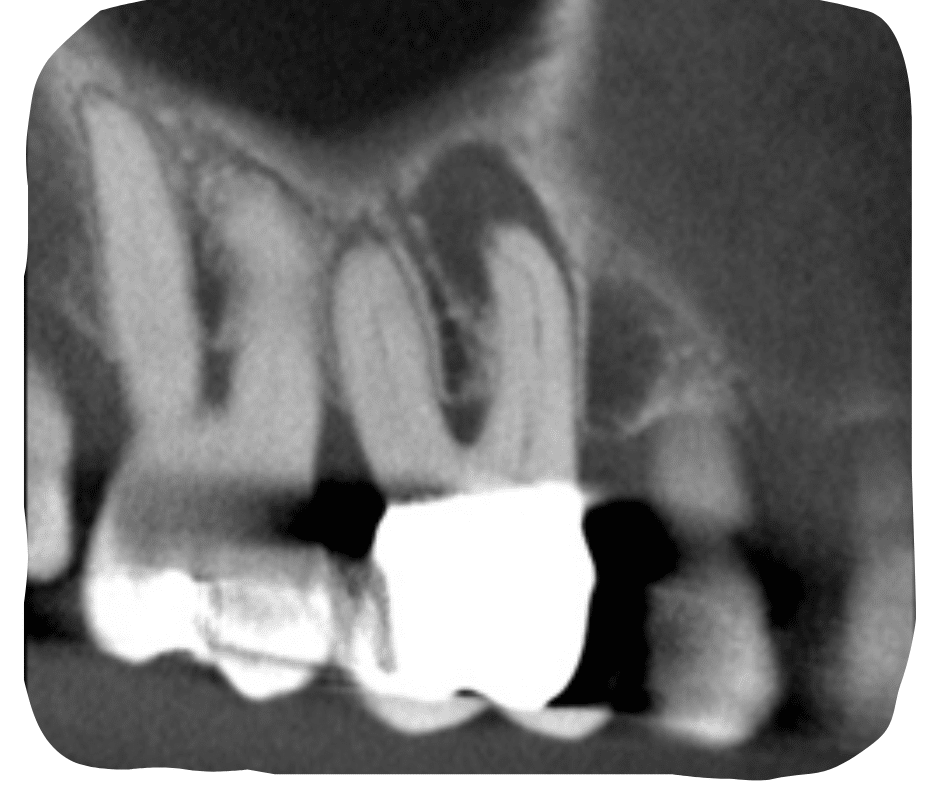

Case Study by Dr. Randy Cross

EndoScore of 3 at finish. Necrotic Symptomatic Apical Periodontitis. 2 visit with triple antibiotic paste, 30x06 conserve file with matching GP and Endoceramic sealer. Finished with bonded VistaApex clear flowable. The patient is being recalled in one year to confirm healing.

EndoScore: 3